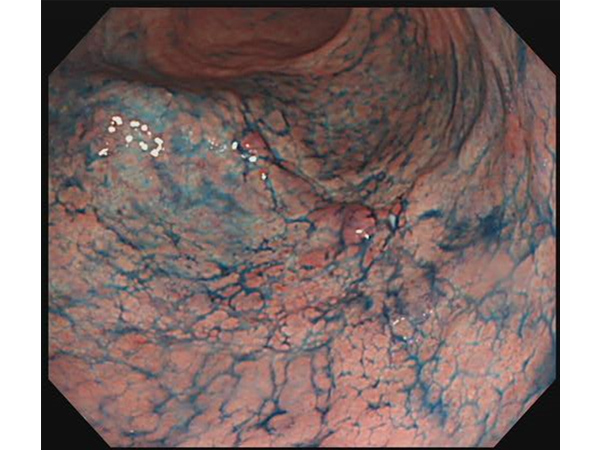

検診で発見した症例

無症状の早期発見の胃がんです。特殊な色素散布(インジゴ散布)により、がんが明瞭になります。